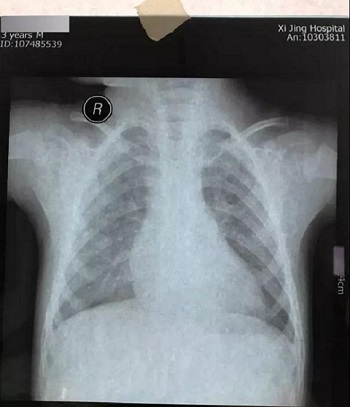

十二、拍摄时,尽可能的将片子上的文字信息拍摄清楚,并将左右拍摄清楚(片子上有标R,表示右侧right,L, 表示左侧left的意思), 每张片子上的文字都能按照阅读习惯拍正确,不要拍反了。

拍摄时,必须要对着片子上的文字对焦, 方向正确,将文字拍摄得清晰可视,保证放大图片后文字依然清晰可见(如下图),尽可能多的保留片子上的信息。